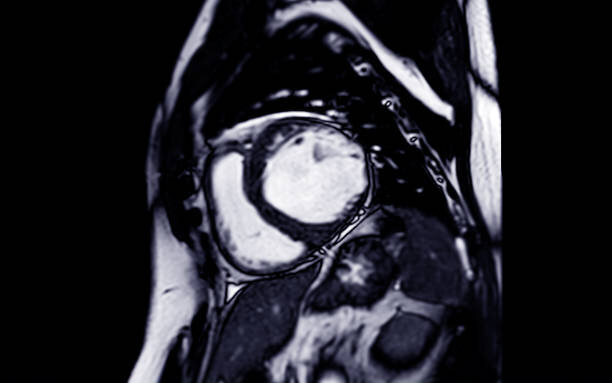

The Heart MRI Scan at Marris Medical uses advanced magnetic imaging to examine the heart in exceptional detail. This test helps evaluate heart rhythm issues, structural abnormalities, and blood circulation efficiency. With no radiation exposure and high diagnostic accuracy, it is a preferred choice for cardiologists aiming to understand complex cardiac conditions and provide effective long-term care.